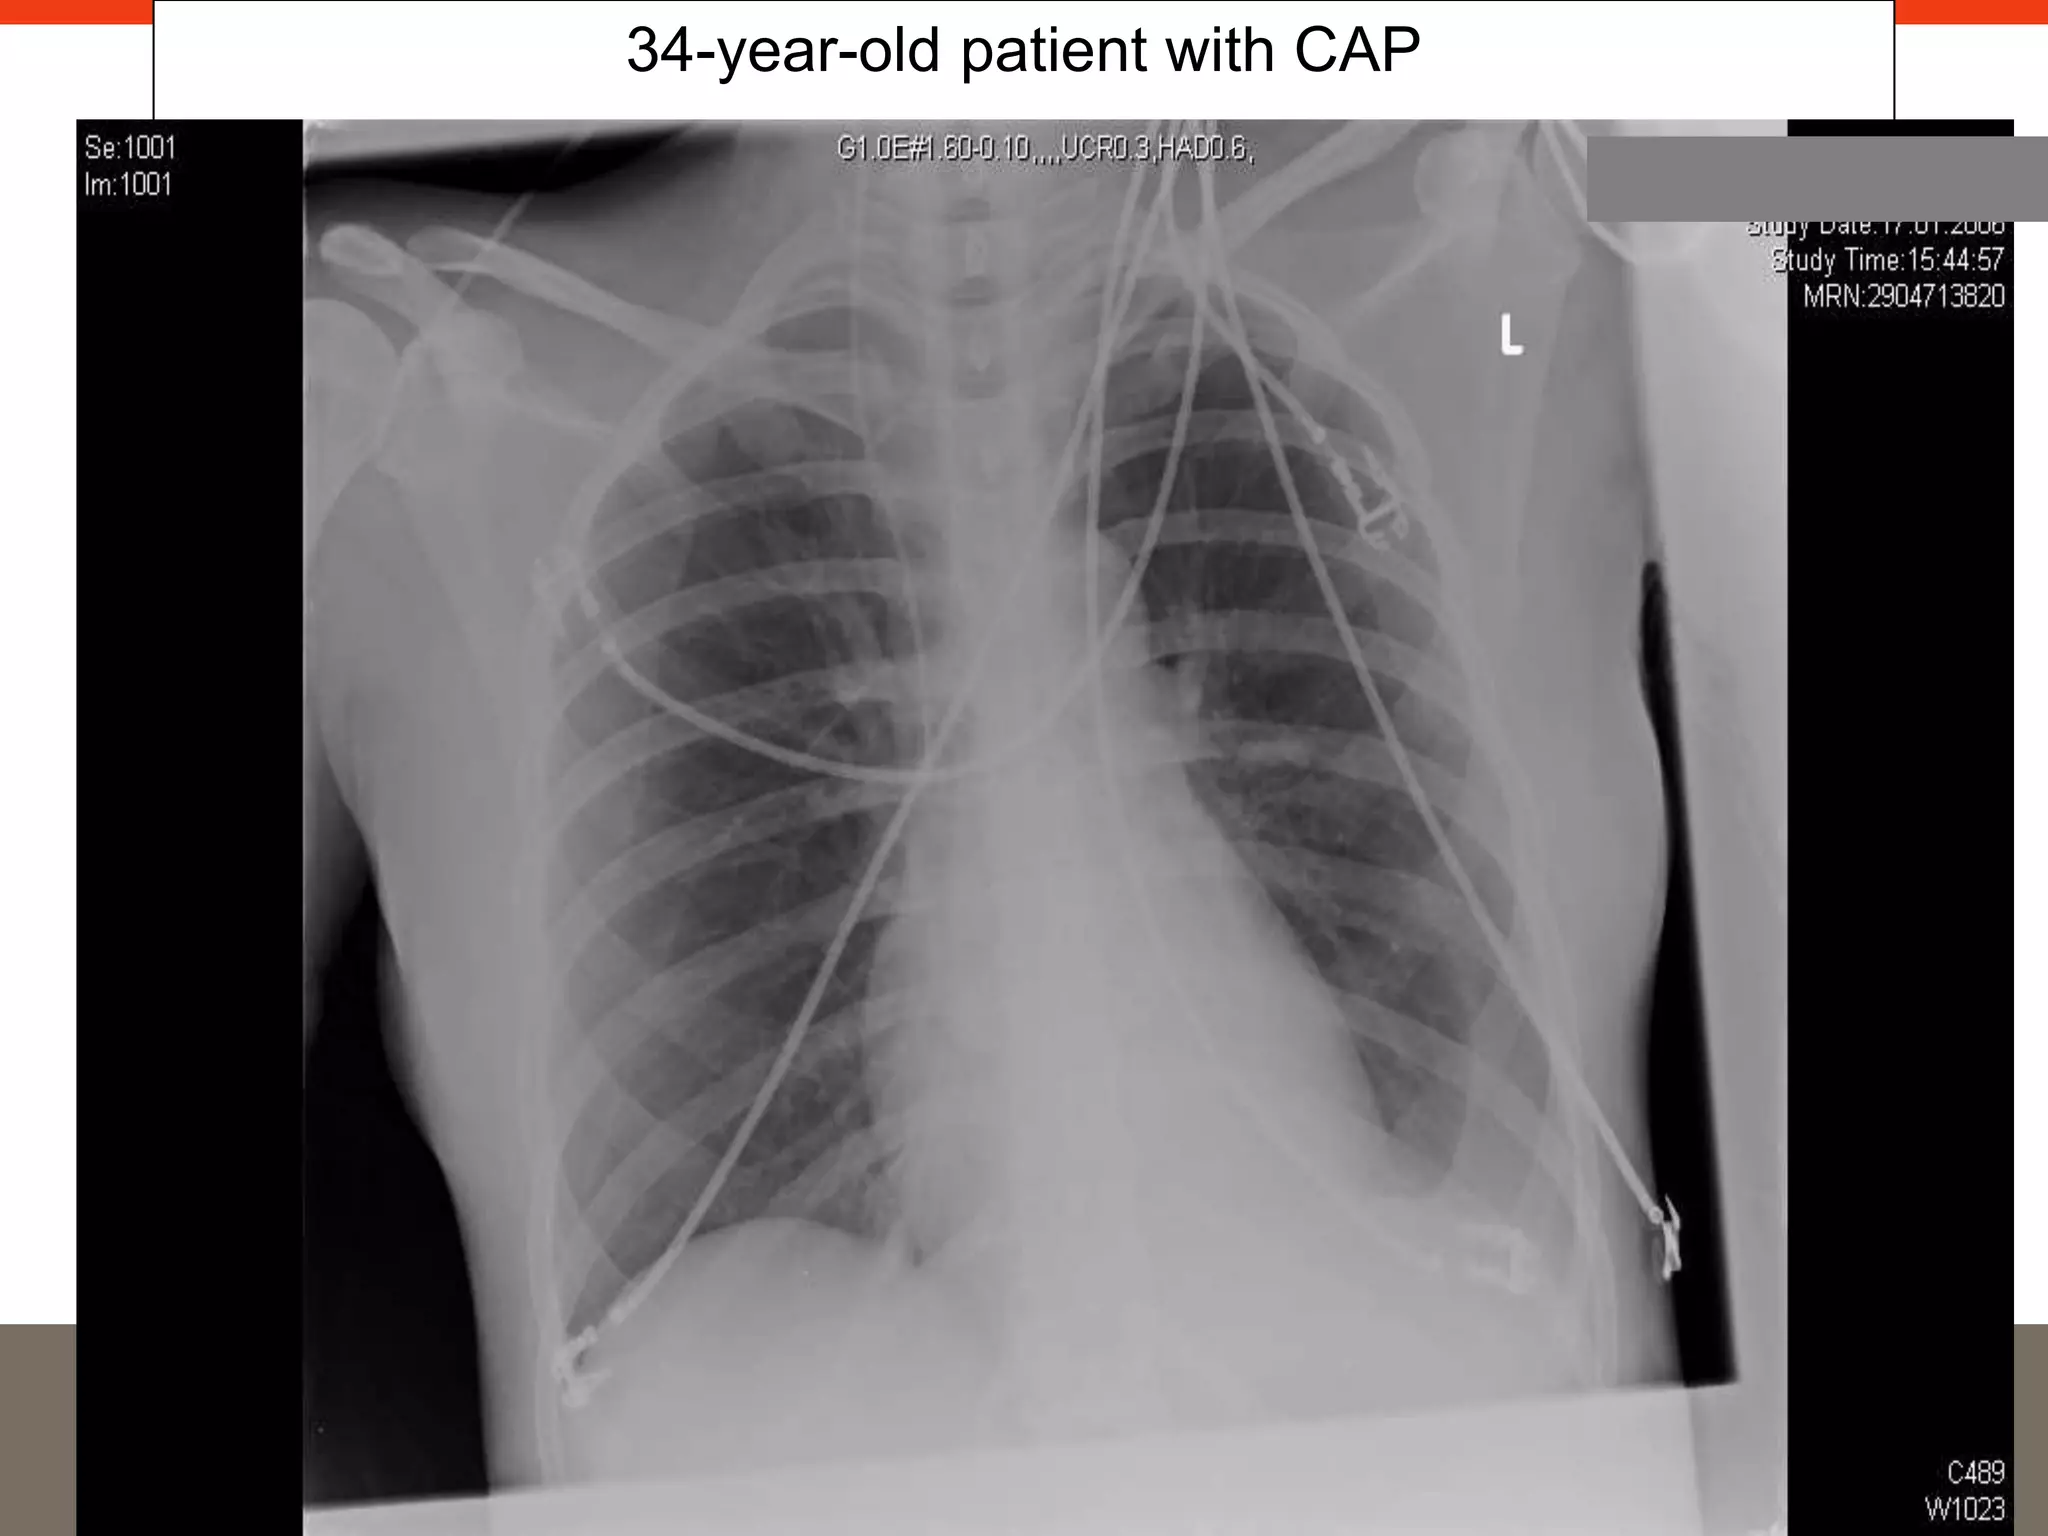

34-year-old patient with CAP

• 23.

34-year-old female, GPvisit after two days of symptoms Biochemistry • WBC 12,800/μL, Hct 34.6%, Platelets 142,000/μL • Sodium 135 mmol/L, Glucose 12.6 mmol/L, BUN 33 mmol/L • CRP 320mg/L, PCT 1.5 μg/L • paO2 65mmHg, paCO2 32mmHg, pH 7.4, HCO3 17.4, SaO2 92%